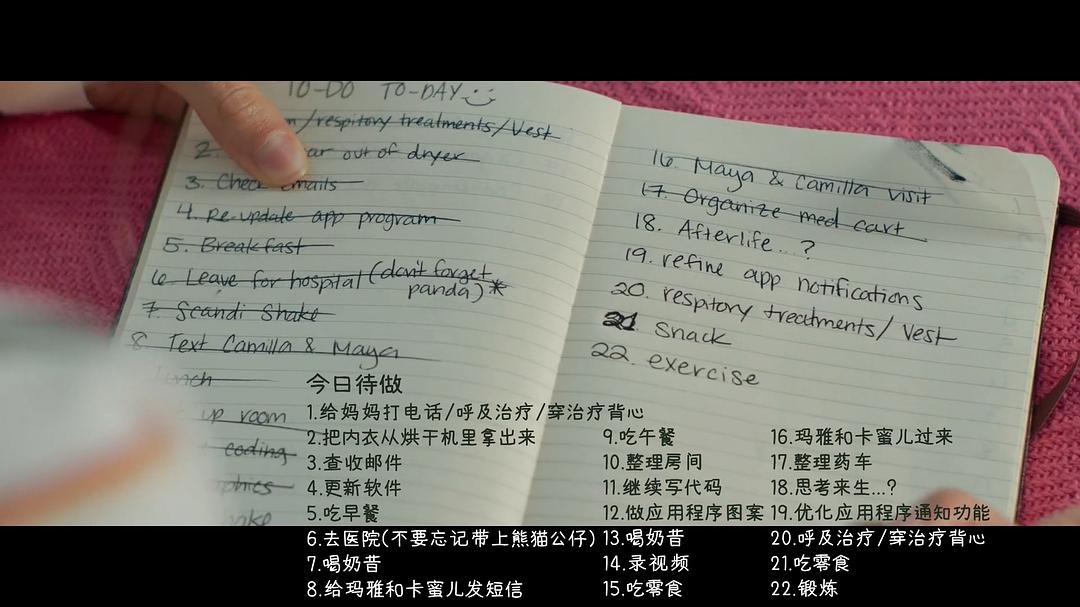

17岁女孩Stella和男孩Will身患囊肿性纤维化疾病,他们在医院治疗的过程中相识相爱,两人必须抓紧每分每秒活着的时间。他们的爱情能够战胜疾病和死亡吗?

17岁女孩Stella和男孩Will身患囊肿性纤维化疾病,他们在医院治疗的过程中相识相爱,两人必须抓紧每分每秒活着的时间。他们的爱情能够战胜疾病和死亡吗?

17岁女孩Stella和男孩Will身患囊肿性纤维化疾病,他们在医院治疗的过程中相识相爱,两人必须抓紧每分每秒活着的时间。他们的爱情能够战胜疾病和死亡吗?